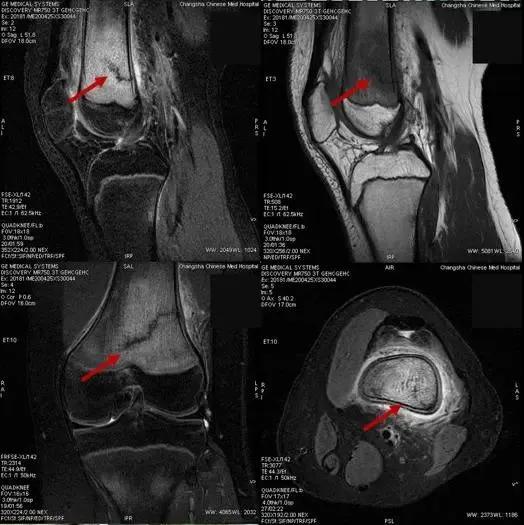

钱金娣主任夏咸林主任影像检查会诊

15岁的罗同学

这名新近返校的初三学生

因临近中考需参加体育考试

每天都进行了

一定强度的体育训练

最近几天出现膝关节疼痛

且有明显加重现象

于是家人带他到医院就诊

诊断为应力性骨折

应力性骨折又称疲劳性骨折或积累性劳损,当肌肉过度使用疲劳后,不能及时吸收反复碰撞所产生的震动,这些低于强度极限的应力反复持久地传导至骨骼,可引起局部骨质的累积性微损伤,最终导致一种特殊类型骨折。学生们应力性骨折常发生在胫骨中上段、股骨颈和股骨中下段。休息是唯一能完全治疗好应力性骨折的方法。通常会用石膏或者保护靴予以保护的状态下彻底休息 4~8 周。一旦医生建议可以开始恢复活动,应遵循医嘱,尽早进行合理的康复锻炼。